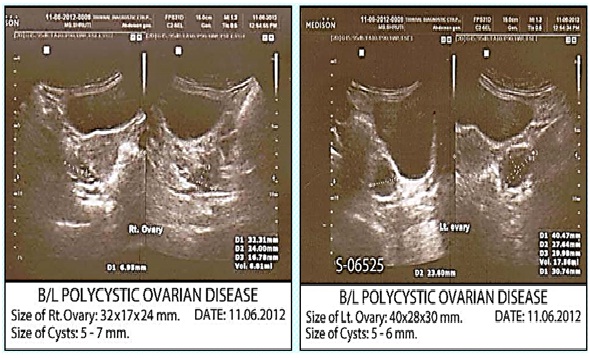

Image: After Treatment.

Menses appeared soon. Patient was over all better. Fear of misfortune and weeping tendency also reduced. Repeat ultrasonography of pelvis revealed normal uterus and ovaries with no evidence of PCOD.

Patient was relieved of the troublesome disease and hence was very satisfied.